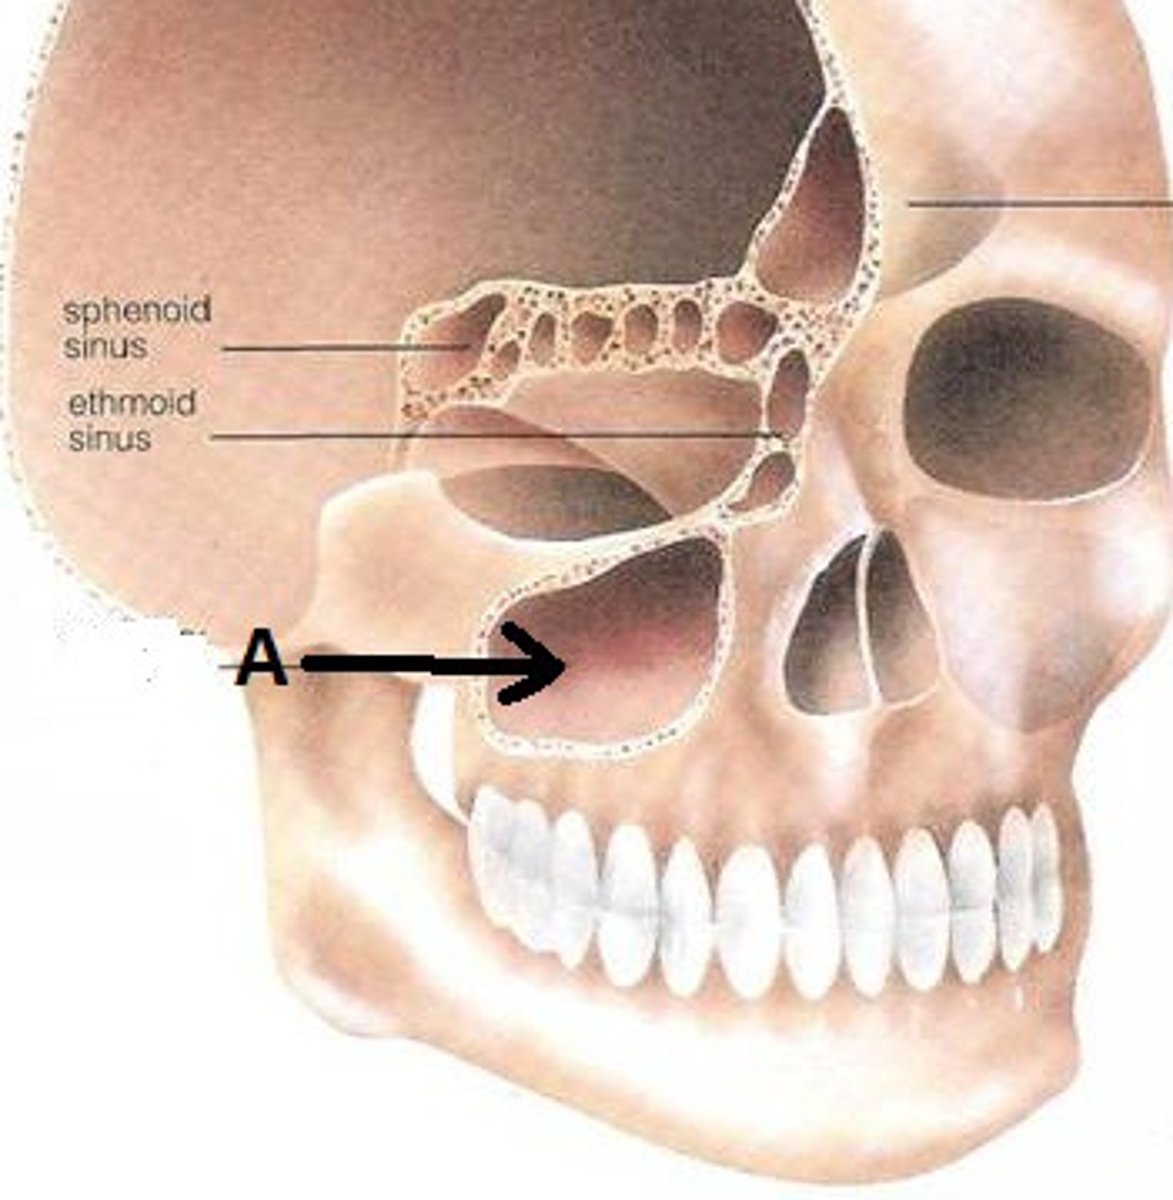

Sphenoid Sinus

Found deep within the skull behind the Ethmoid sinuses. They are small cavities approximately the size of a large grape. The left and right sit next to each other and are separated by a thin plate of bone (septum).

Ethmoid Bone

Forms part of the posterior portion of the nose, the orbit, and the floor of the cranium

Maxillary Sinus

Largest paranasl sinus; pyramidal; on cheek bone lateral to nasal bone